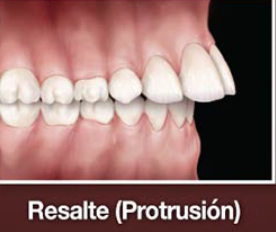

En la relació sagital a nivell incisal té un overjet amb augment del ressalt, ja que mesura més de 3 mm el ressalt, i l'overbite és a dir sobremossegada és negativa, ja que hi ha una mossegada oberta, anterior. I en la relació transversal molar té una mossegada normal.

Es caracteritza per un desenvolupament vertical, amb una disminució del perímetre disponible per les dents permanents, per al que tindrem apinyament dentari i/o protrusió per falta d'espai.